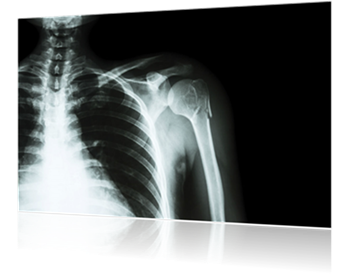

Anatomy of the Shoulder

The shoulder is a ball and socket joint with three bones including shoulder blade or scapula, collarbone and upper bone or humerus. These bones are joined together by muscles, ligaments and tendons. The shoulder joint has the great range of motion among all the joints in the body. Due to this, the shoulder is susceptible to an injury, especially the acromioclavicular joint that is located on the top of the shoulder.

In order to correctly diagnose a shoulder injury the doctors may order tests such as X-Rays, MRIs and CAT scans. Depending on the severity of the injury, the treatment may be as simple as use of a sling to immobilize the shoulder and hold it in place to reduce pain and promote healing.